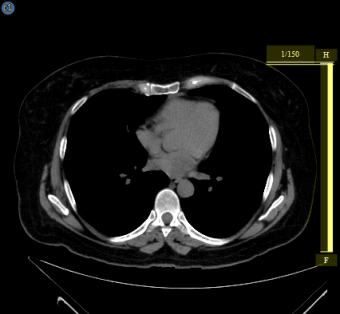

The stack ruler shows where the current image is located with respect to other images in the series. The stack ruler appears as an overlay along the edge of the image frame and shows the relative position of the currently displayed image within the series. It is shown highlighted in yellow in the image below.